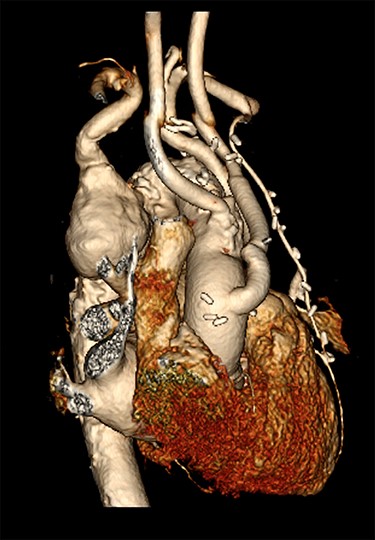

A 78-year-old male presented with sudden onset tearing chest pain with radiation to the back and associated dyspnoea and dysphagia. This was on a background of ischaemic heart disease, hypertension, hypercholesterolaemia and previous small bowel resection for neuroendocrine mesenteric malignancy. He was an ex-smoker with no personal or family history of connective tissue disorders. On computed tomography angiography (CTA) he was found to have an aberrant right subclavian artery (SCA), coursing posterior to the trachea and oesophagus, with an associated 4.4 cm Kommerell’s diverticulum (Fig. 1). Imaging also illustrated tracheal stenosis and oesophageal compression. A coronary angiogram demonstrated severe double vessel coronary artery disease. A staged procedure with aortic arch debranching and coronary artery bypass grafting (CABG), followed by a thoracic stent graft and amplatzer plug to address the Kommerrel’s Diverticulum was planned.

Computed tomography (CT) reconstruction illustrating Kommerell’s diverticulum and an aberrant right subclavian artery.